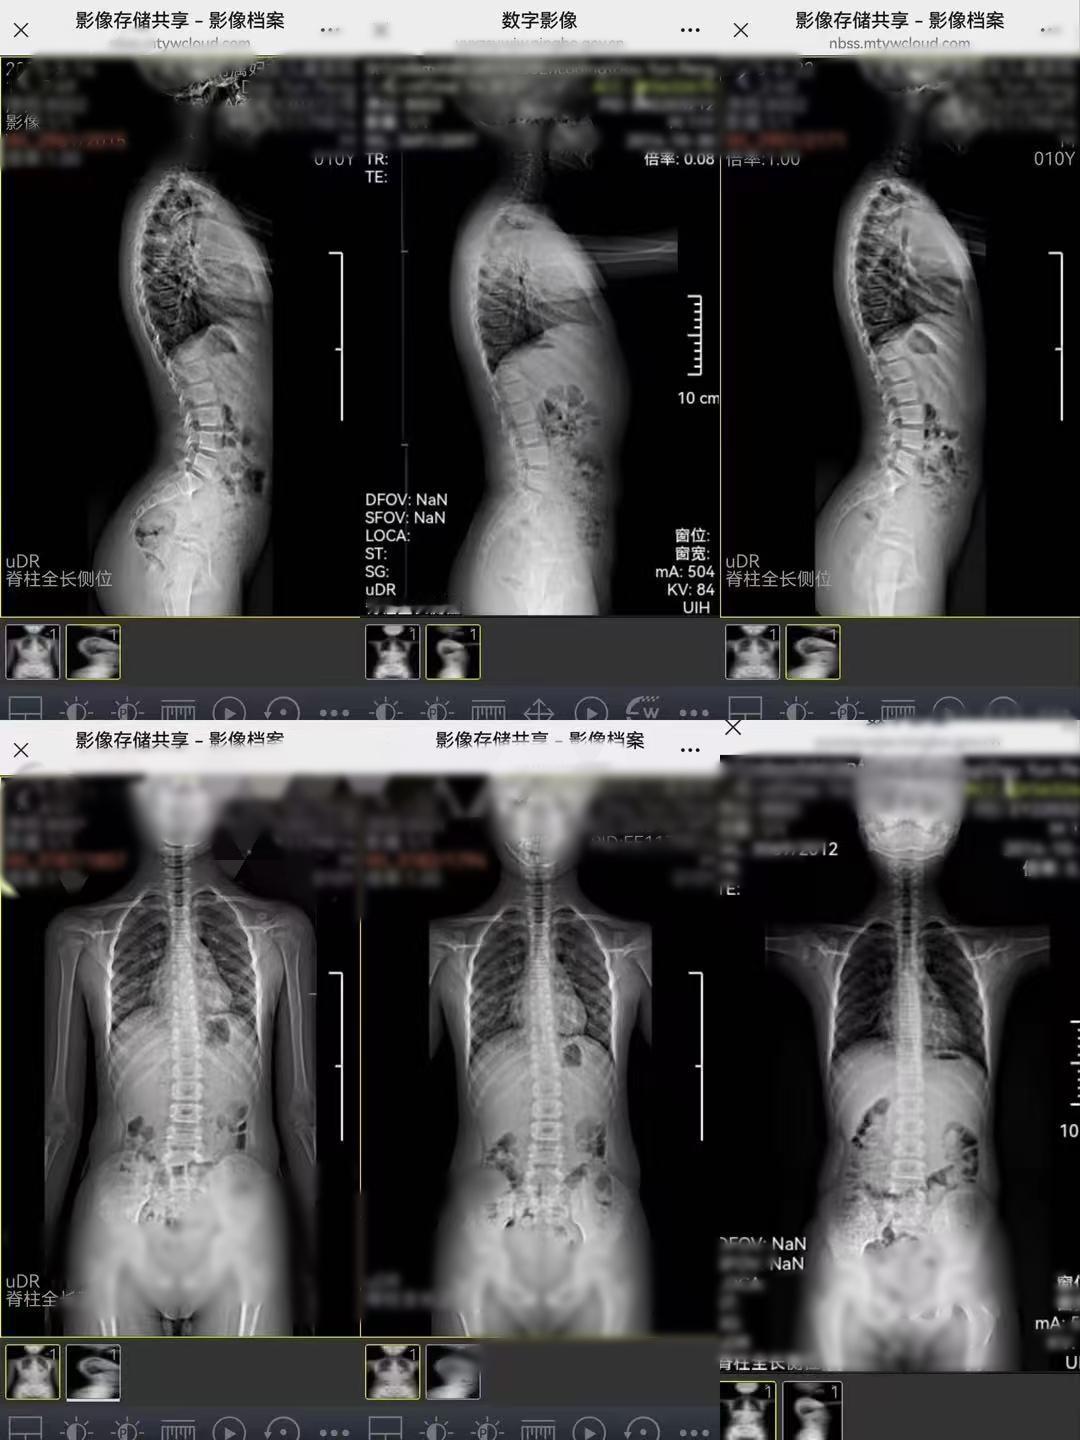

脊柱侧弯 今日份好消息——在杭州店纠正脊柱侧弯的小朋友,从去年3月一直到现在,都在坚持日常康复,脊椎也有了变化

脊柱侧弯如果长期不干预,不只是体态不好看,它是一个会慢慢“拖累”全身的结构性问题,潜在风险会随着年龄和度数增加而放大,尤其是正值发育期的小朋友,一定要格外注意健闻登顶计划锐博康复 杭州·锐博运动康复(杭州店)